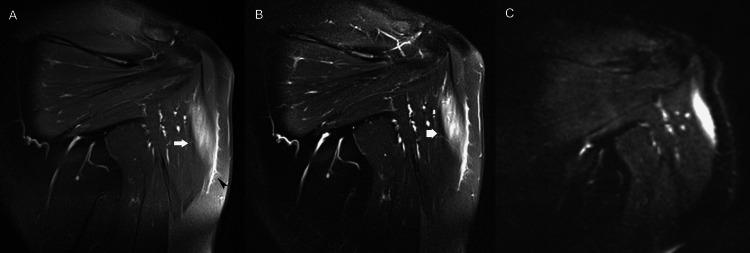

Skeletal muscle is a major anatomic structural component of the human body. Myopathy, defined as skeletal muscle disease, may offend any of the body's 650 muscles and encompasses an extended array of acute and chronic abnormalities. Muscle disease can be categorized according to etiology as congenital, traumatic, infectious, or neoplastic. The concept of the diversity of multiple muscular disease processes signifies an important role for imaging in the detection and characterization of myopathy. However, despite the exquisite physiological properties of skeletal muscle, muscle imaging has not received attention equal to that of bones and joints. Accordingly, this article provides an indication of the most suitable imaging modalities for myopathy and reviews a multitude of primary and systemic muscle derangements, with an emphasis on magnetic resonance (MR) imaging findings. Because these patterns of MR imaging abnormality bespeak the widespread nature of myopathy, we illustrate typical examples of muscle disease processes to simplify diagnosis.

骨骼肌是人体主要的解剖结构组成部分。肌病,定义为骨骼肌疾病,可累及人体650块肌肉中的任何一块,涵盖一系列急性和慢性异常情况。肌肉疾病可根据病因分为先天性、创伤性、感染性或肿瘤性。多种肌肉疾病过程的多样性概念表明成像在肌病的检测和特征描述中具有重要作用。然而,尽管骨骼肌具有精细的生理特性,但肌肉成像并未得到与骨骼和关节成像同等的关注。因此,本文指出了最适合用于肌病的成像方式,并综述了多种原发性和全身性肌肉紊乱,重点关注磁共振(MR)成像表现。由于这些MR成像异常模式表明肌病具有广泛的性质,我们展示了肌肉疾病过程的典型例子以简化诊断。